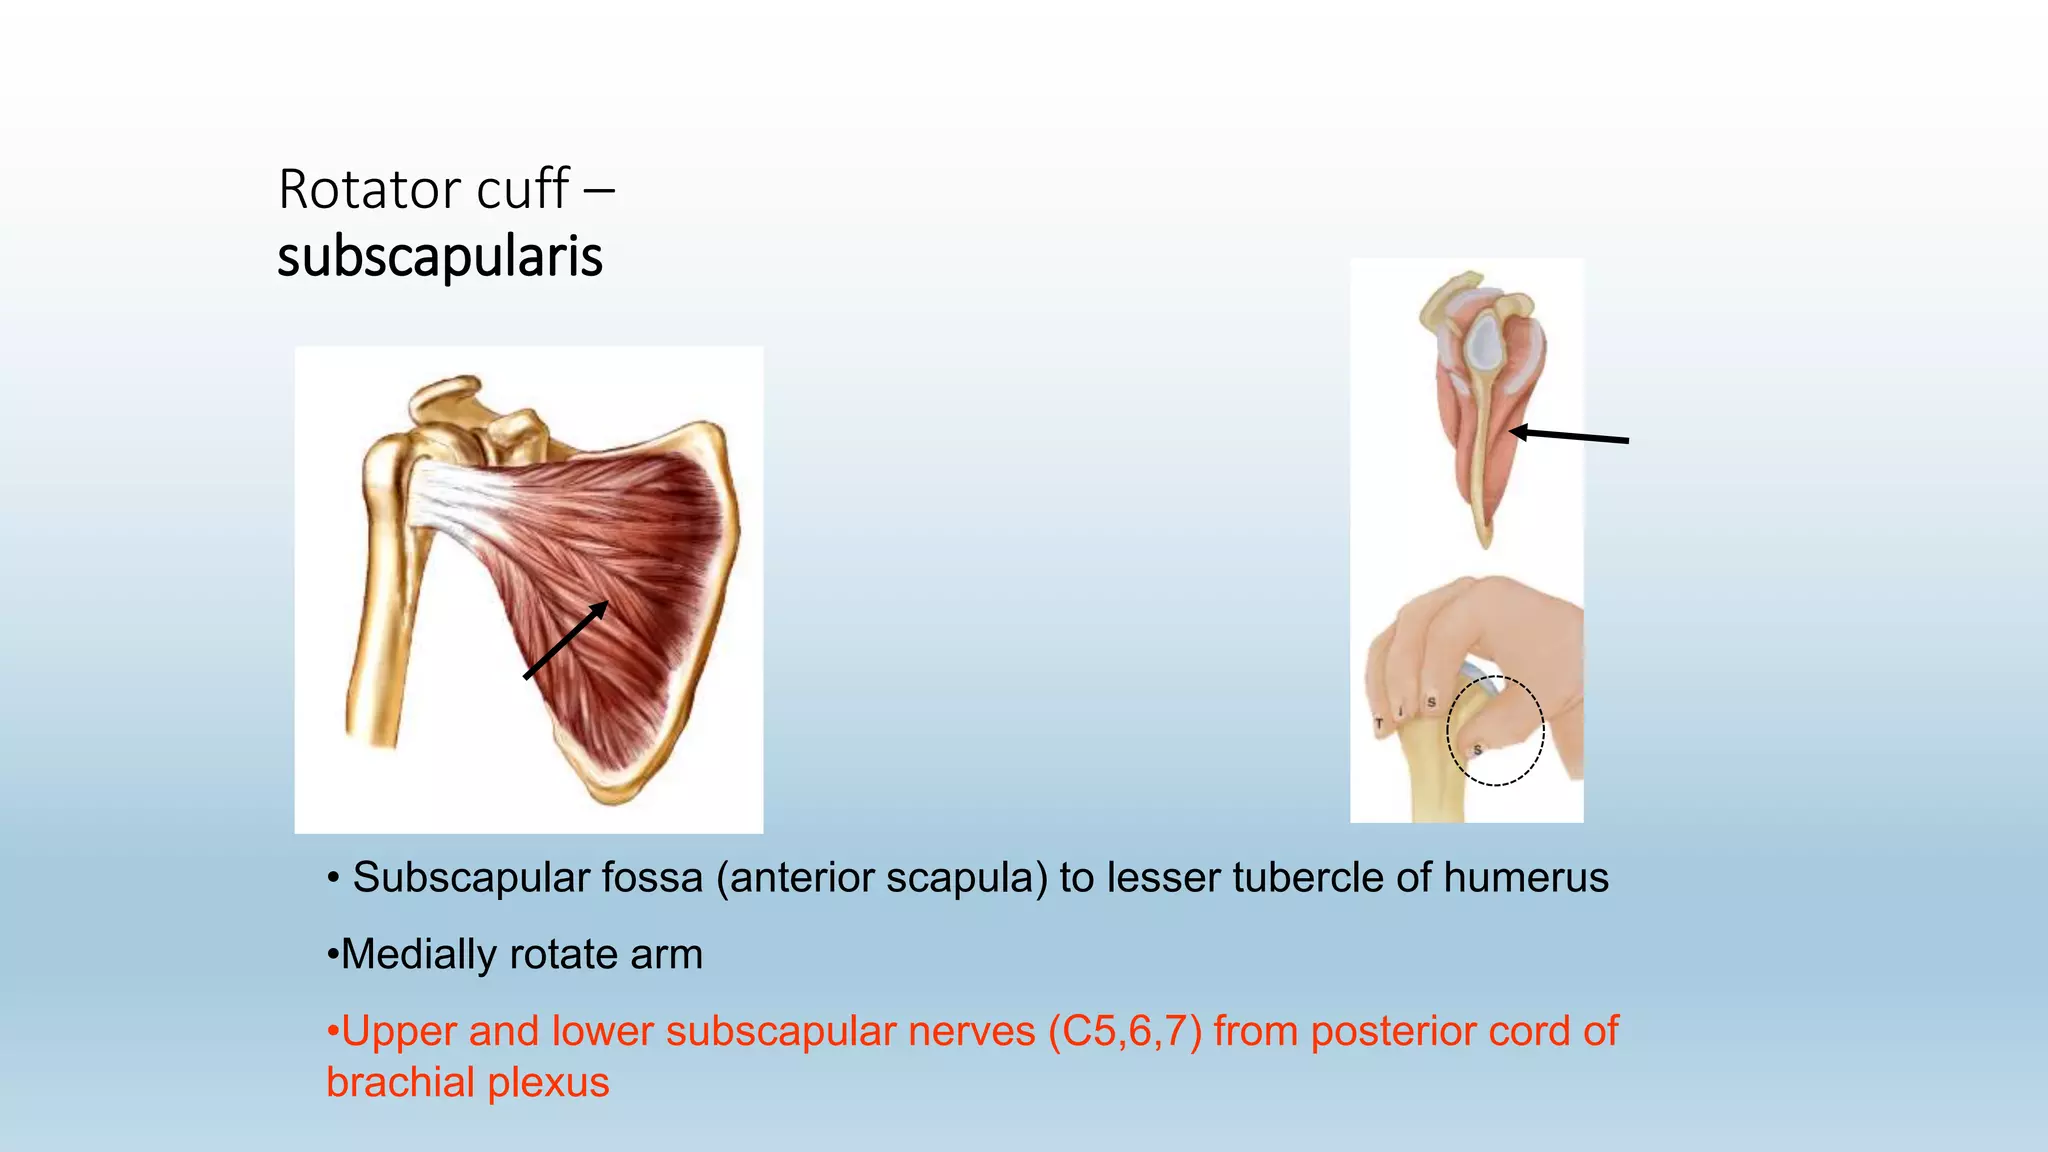

The document summarizes an anatomy revision session on the upper limb. It discusses various muscles of the upper limb including their origins, insertions, innervations and functions. Key muscles covered include the pectoralis major and minor, serratus anterior, deltoid, biceps brachii, brachialis, coracobrachialis, and triceps. It also discusses the rotator cuff muscles and muscles of the forearm including flexor carpi ulnaris and radialis. The session aims to help students identify upper limb muscles and understand their relations to nerves.